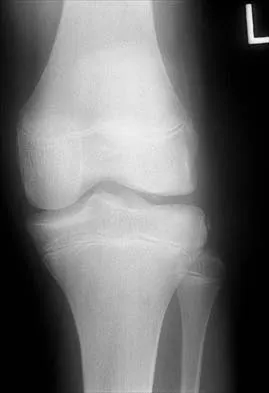

An 8-year-old girl was treated for a Salter-Harris type I fracture of the right distal femur 2 years ago. Examination reveals symmetric knee flexion, extension, and frontal alignment compared to the contralateral knee. She has 1-cm of shortening of the right femur. History reveals that she has always been in the 50th percentile for height, and her skeletal age matches her chronologic age. Radiographs are shown in Figure 9. What is the expected consequence at maturity?

Explanation

The child has a near complete central physeal arrest of the distal femur and worsening limb-length discrepancy will develop. She is growing at the average rate for the population. The distal femoral physis grows at a rate of roughly 9 mm per year. Girls finish their growth at approximately age 14 years. Thus, at maturity the left leg will be 6.4 cm longer than the right. An angular deformity has not developed at this point and her arrest is central; therefore, angular deformity is unlikely to develop in any plane. Little DG, Nigo L, Aiona MD: Deficiencies of current methods for the timing of epiphysiodesis. J Pediatr Orthop 1996;16:173-179.